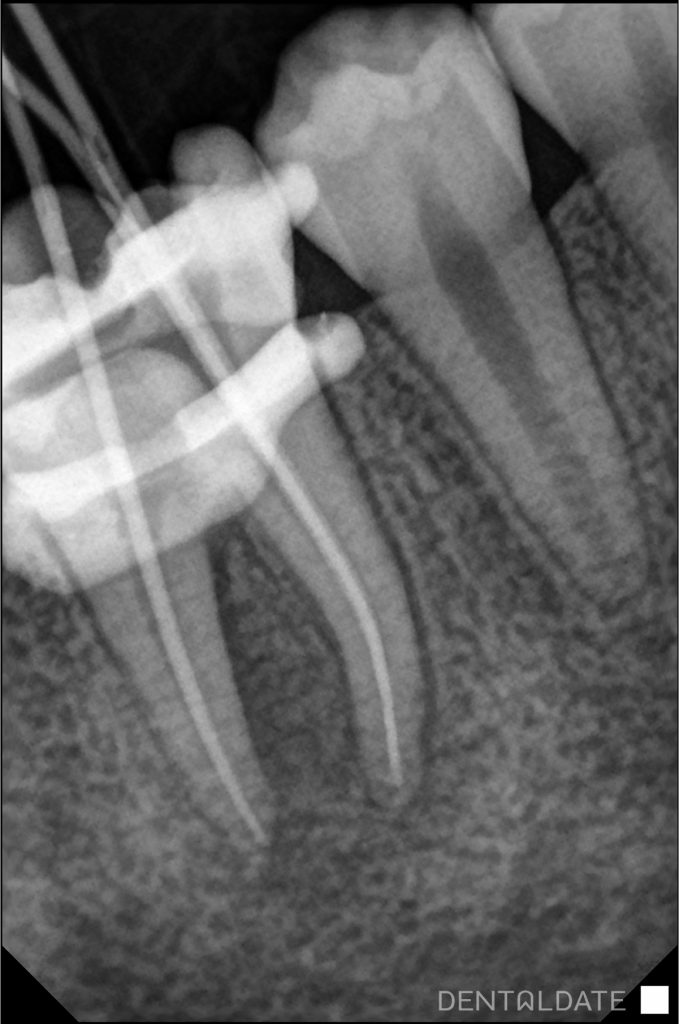

Endodontic re-treatment of tooth 4.6 was performed. The root canals of the tooth were filled, passed and treated for the whole length of the root, with intermediate placement of Calcium hydroxide in the canals for 3 weeks.

After a period of time the fistulous passage disappeared. A periapical photograph was taken, which showed a marked improvement of the rarefaction in the bone around the roots of the tooth.